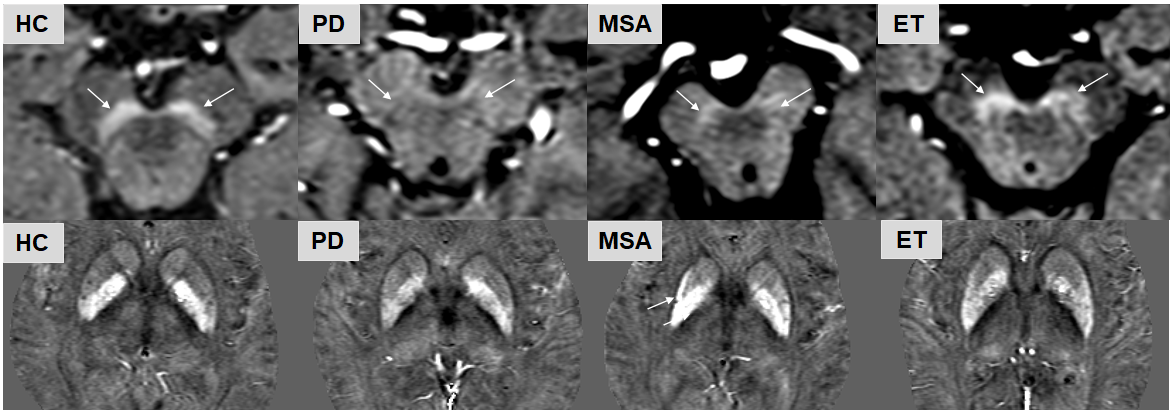

There were no significant differences in age for the MDS or HC groups in either Cohort 1 and Cohort 2, but the gender for the ET group in Cohort 1 and for the MSA group in Cohort 2 were significantly different than the other groups. There were multiple differences between the groups with respect to both iron and NM in the SN, RN and putamen. These are summarized in Table 2. Specifically, the key findings were as follows. The thresholded NM signals in the bilateral SN decreased in both the PD and MSA groups when compared with the HC or ET groups (Figure 1). The bilateral SN iron deposition increased in the PD and MSA groups compared to the HCs. The SN iron difference between the PD and ET groups was significant but not between the MSA and ET groups. Interestingly, the bilateral RN susceptibility were increased for the MSA group as compared with the control group, but not for the PD or ET group. Another important finding was the bilateral PUT atrophy and increased iron in the left PUT for the MSA group compared with all the other groups (Figure 1). These findings were equally valid in both cohorts.

Figure 1. The top row (NM-MRI) shows the neuromelanin in the SNpc for a control, and patients with PD, MSA, and ET respectively. The NM loss in the patient with PD and the one with MSA is very obvious compared with the control and the patient with ET. The bottom row (QSM) shows the basal ganglia susceptibility. The posterior part of the PUT shows a high level of iron content in the patient with MSA. Moreover, the PUT (especially the right side) is atrophied.